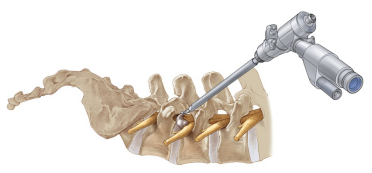

經皮椎間孔鏡椎間盤切除術(percutaneous transforaminal endoscopic discectomy,PTED)是治療腰椎間盤突出癥的一項新的微創技術。與傳統開放式椎間盤切除術相比,擁有創傷小、出血少、術后康復快、疤痕小等優點。

椎間孔鏡構造類似于關節鏡,手術全程采用影像定位、高清視頻監控,將復雜的操作簡單化,將危險的手術安全化。猶如腹腔鏡摘除膽囊一樣,小切口高、精、準完成大手術。是目前治療腰椎間盤突出癥最先進、最微創、切口最小、效果最好、恢復最快、最經濟的手術。

腰椎間盤突出導致的坐骨神經痛。即使是復發性椎間盤突出和由突/脫出的椎間盤碎塊導致的椎間孔狹窄也可以做。